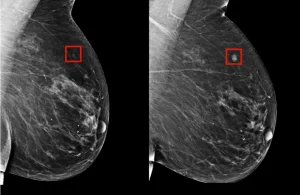

1. Mammografi

Mammografi, meme kanserini erken aşamada tespit etmek için kullanılan röntgen tabanlı bir tarama yöntemidir.

1. Mammografi Tarama

Her kadının yaşına, risk faktörlerine göre düzenli olarak mammografi yaptırması önerilir. Mammografi, erken evrede küçük kitleleri tespit edebilir.